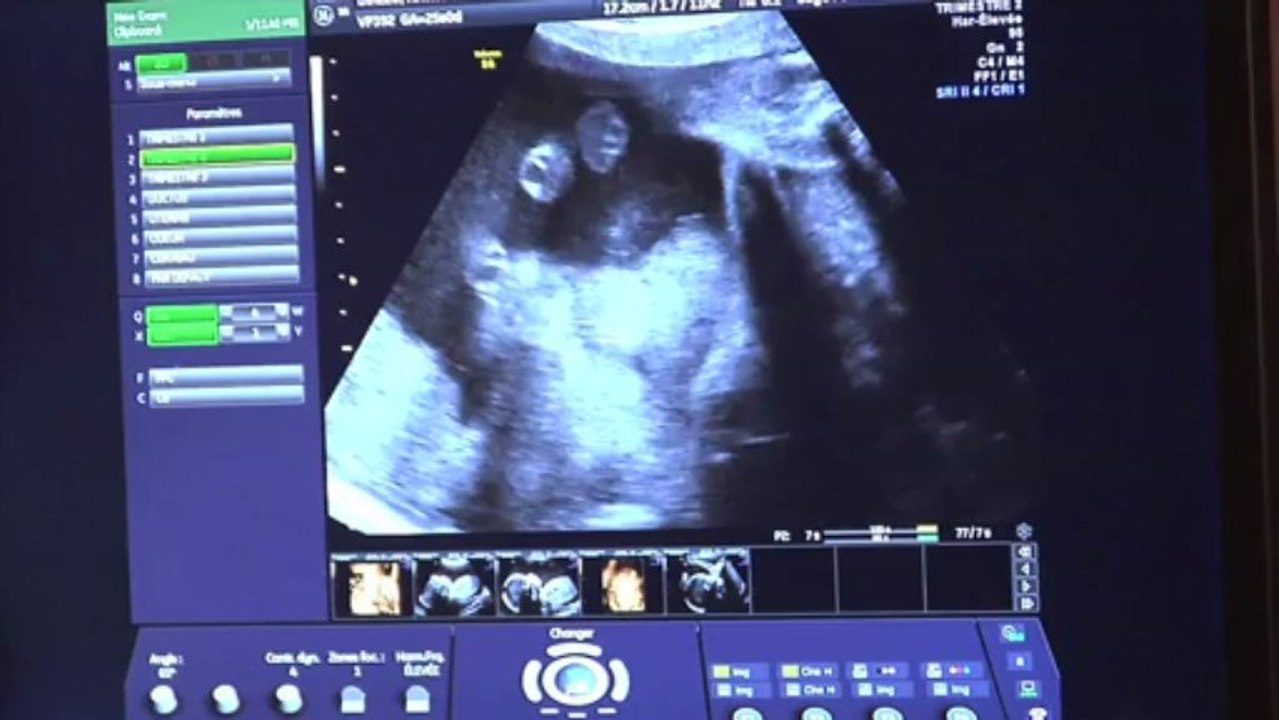

Source: afppmeipy.pages.dev Echographie du 2eme trimestre 18/10/08 Amelie et Nicolas accouchement prévu le 31 janvier 2009 , L'échographie morphologique du deuxième trimestre, effectuée généralement entre 20 et 25 SA (semaines d'aménorrhée), autour de la 22ème semaine, est un examen clé de la grossesse․ Elle permet une évaluation approfondie du développement fœtal․ Au cours de cette échographie morphologique, un gynécologue-obstétricien examine minutieusement l'entièreté du fœtus, à la recherche d'éventuelles anomalies de structure ou de fonction, ou de.

Source: tidyboxwse.pages.dev Ecografía fetal en el segundo trimestre de embarazo de interés para el cirujano pediatra , L'échographe va regarder chaque organe un à un en commençant par le coeur. Les principaux objectifs de l'échographie morphologique du 2e trimestre sont le dépistage de certaines pathologies et la localisation du placenta.« On va vérifier la mobilité du fœtus, son activité cardiaque et prendre un certain nombre de mesures biométriques : le diamètre bipariétal, le périmètre crânien, le diamètre.

Source: gnnustchmo.pages.dev mes presques riens Echographie du 2ème trimestre écho morpho , Au cours de cette échographie morphologique, un gynécologue-obstétricien examine minutieusement l'entièreté du fœtus, à la recherche d'éventuelles anomalies de structure ou de fonction, ou de. Echographie 2eme trimestre, appelée aussi échographie morphologique